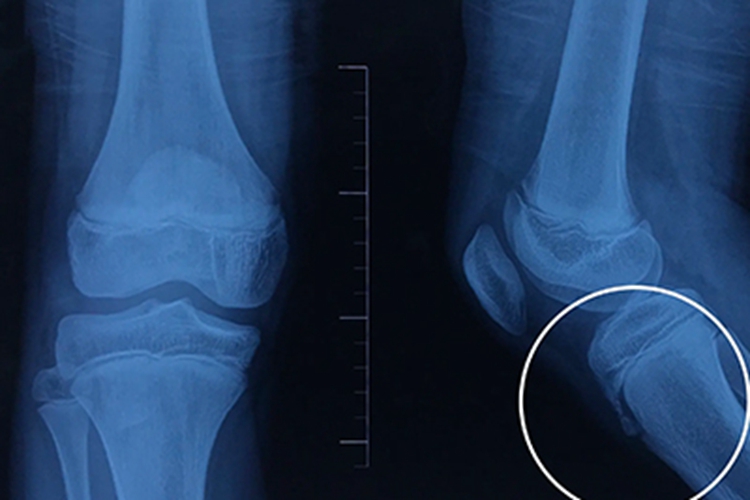

胫骨结节炎临床表现为膝痛,行走时明显,上下楼梯时加重。X线片显示胫骨结节骨骺呈舌状,骨骺骨质致密,或骨骺边缘不规则,附近软组织肥厚,或见骨骺碎裂与骨干分离。体格检查发现一侧或双侧胫骨结节上端前方局限性肿胀,压痛明显,晚期胫骨结节肥大突起,对股四头肌抵抗阻力运动引起局部疼痛加重。